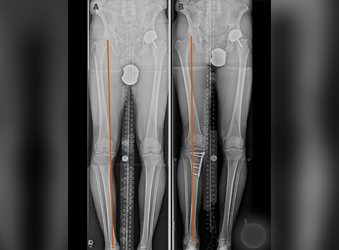

Deformity correction using the Ilizarov method is a surgical procedure that involves the use of an external fixator to realign bones and joints in the body.

HTO (High Tibial Osteotomy) is a surgical procedure used to treat knee osteoarthritis by realigning the knee joint. Ilizarov is a type of external fixation device that is commonly...

Polio is a viral infection that can lead to muscle weakness and paralysis. In some cases, it can cause significant deformities of the legs, including limb length discrepancy...